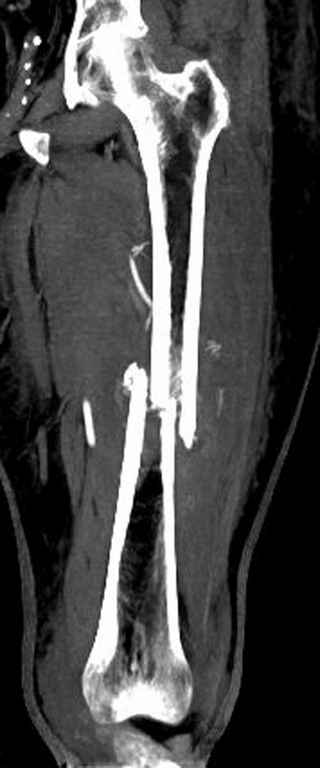

Здесь случай 66 летней пациентки со спонтанными болями в левой нижней конечности, обратилась в приемное, сделаны снимки бедра и КТ.

Патологический перелом бедра, конечность на вытяжении.

Со слов, больная ничем не болела, только последние 3 месяцев чувствовала боли в бедренной области. КТ брюшной полости подтвердил увеличенную правую почку. (5-6)

Для предупреждения кровотечения во время рассверливания, за день до операции провели эмболизацию сосудов питающий метастаз. http://radiology.rsnajnls.org/cgi/reprint/150/3/673.pdf (7-11, 12-15-16)

С минимальным рассверливанием и ретроградным методом провели остеосинтез бедра 12 мм гвоздем. (17-20)